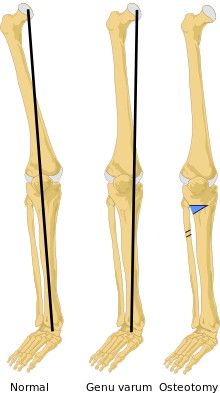

On projectional radiography, the degree of varus or valgus deformity can be quantified by the hip-knee-ankle angle,[6] which is an angle between the femoral mechanical axis and the center of the ankle joint.[7] It is normally between 1.0° and 1.5° of varus in adults.[8] Normal ranges are different in children.[9]

Treatment for children with Blount's disease is typically braces but surgery may also be necessary. In children guided growth surgery is used to gradually correct/straighten the bow legs.[10] For teenagers osteotomy or bone cutting is often used to correct the bone deformity. The operation consists of removing a piece of tibia, breaking the fibula and straightening out the bone; there is also a choice of elongating the legs. If not treated early enough, the condition worsens quickly.[11]